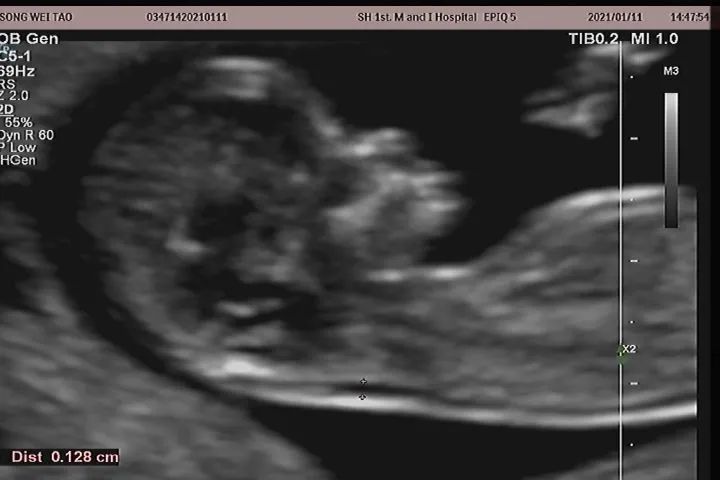

NT是nuchal translucency的缩写,又称颈项透明层扫查,是指胎儿在自然状态下,正中矢状切面的时候,颈后皮下组织内无回声带的最大厚度。

在孕14周之前,胎儿的淋巴系统没有发育完全,淋巴液聚集在颈部淋巴管内,形成了无回声带,而在14周之后,随着淋巴系统发育完全,淋巴液被引流至颈内静脉,NT也就随之消失了。因此,NT检查的最佳时间段是在孕11周-13+6周之间,胎儿头臀长范围在45-84mm之间时进行,当然,在这个时间范围内,胎儿越大,对于结构的显示就越清晰,因此,各位准妈妈也不用着急,这项检查并不是越早越好。2

大家平常最常听到的异常就是NT增厚,随着胎儿大小的变化,NT值的正常上限也在波动,对于非专业人士,我们只要记住,在整个检查时间段内,最厚均不超过3mm。